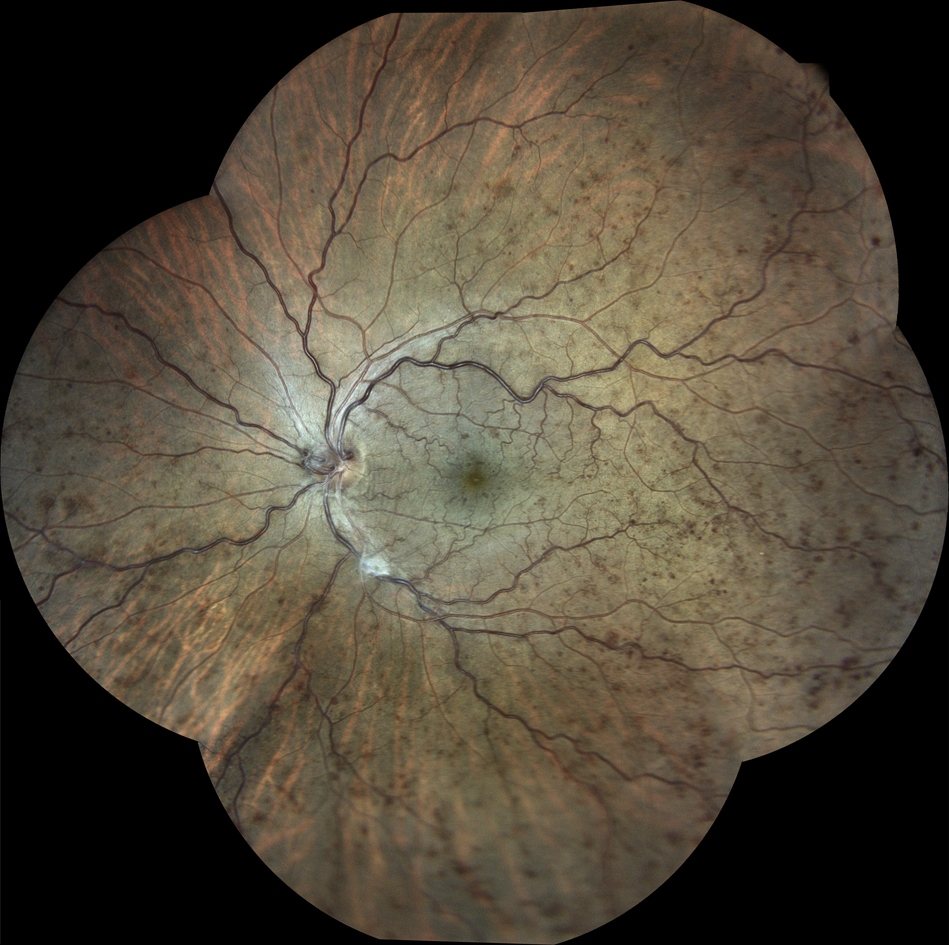

Figure 1. Image of a scleral buckle taken with the Daytona Plus (Optos). Photo credit: Jeffry Gerson, OD, FAAO.